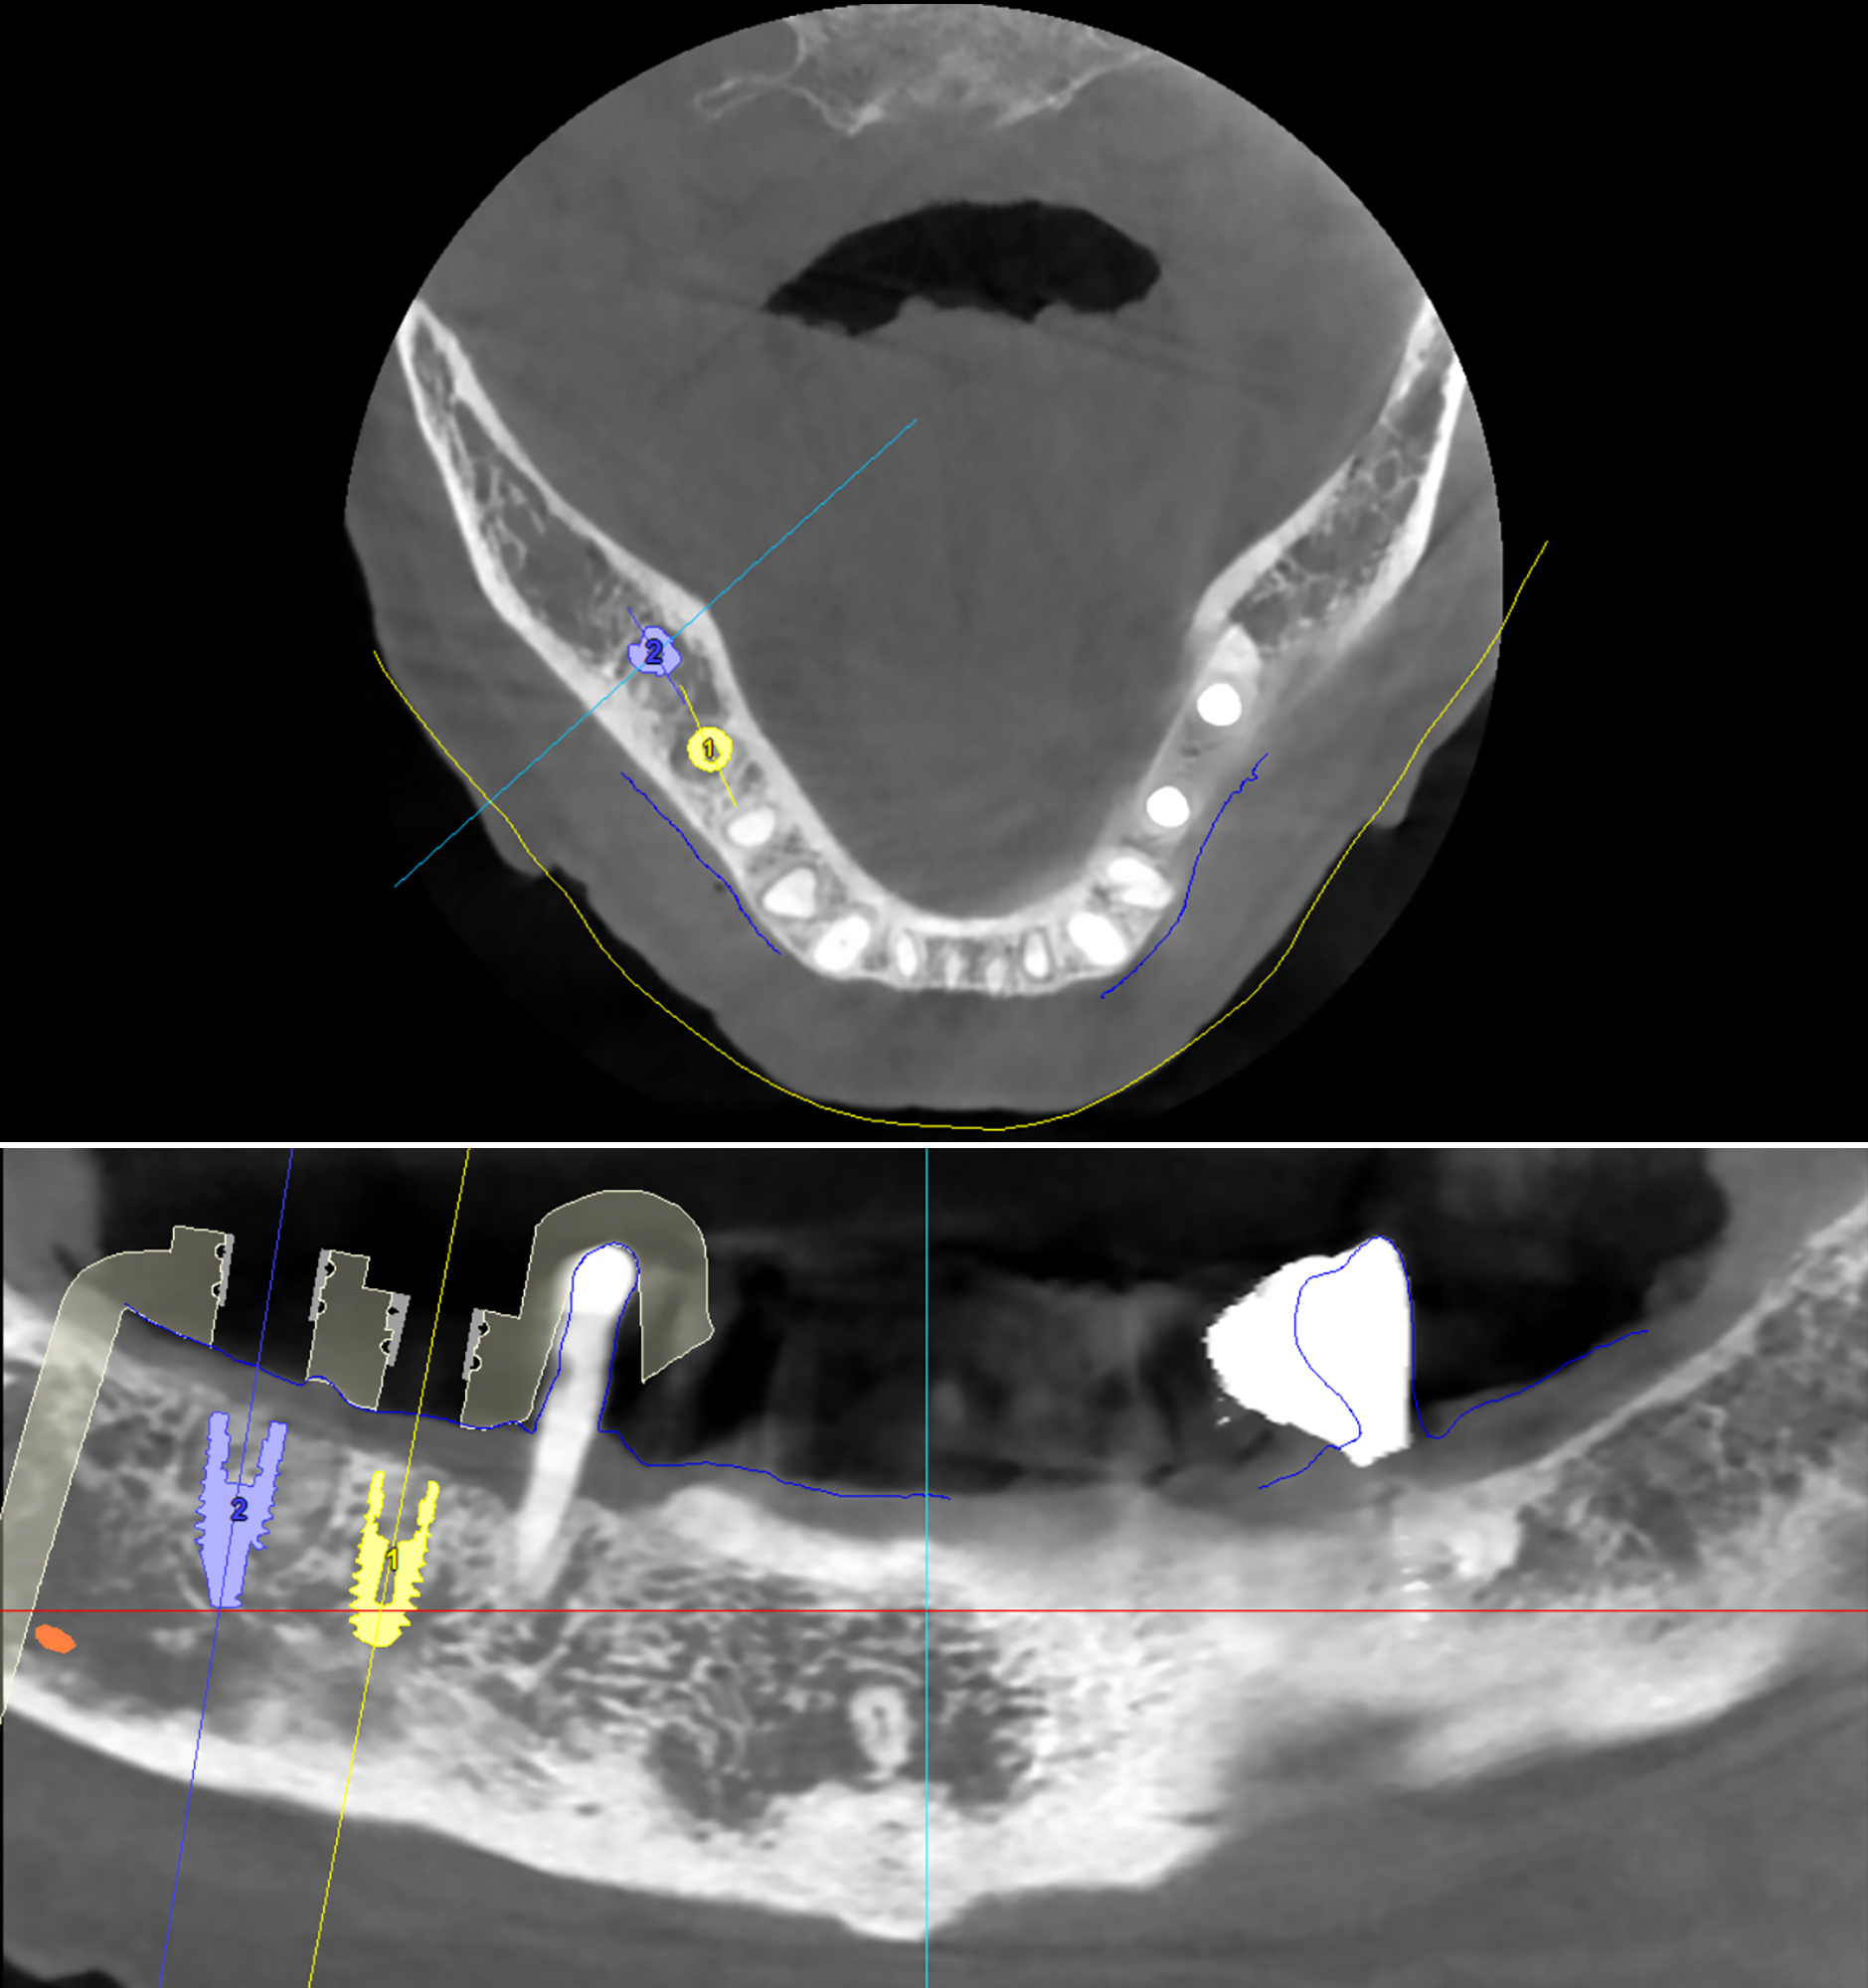

3D αξονική τομογραφία – Πανοραμική και εγκάρσια τομή της κάτω γνάθου της ασθενούς - Η τοποθέτηση των δύο εμφυτευμάτων έγινε στις ιδανικότερες θέσεις, με τη βοήθεια εξειδικευμένου λογισ�μικού χειρουργικού σχεδιασμού που χρησιμοποιούμε για την ακρίβεια και την ασφάλεια κάθε εμφυτευματικού περιστατικού

3D αξονική τομογραφία – Εγκάρσιες τομές της κάτω γνάθου της ασθενούς.

Απεικονίζονται τα δύο εμφυτεύματα που τοποθετήθηκαν με τη βοήθεια εξειδικευμένου προεγχειρητικού λογισμικού. Μέσω της ανάλυσης μπορούμε να αξιολογήσουμε τη θέση τους στο οστό, τον προσανατολισμό και τις μεταξύ τους κλίσεις, καθώς και την πιθανή γειτνίασή τους με σημαντικά ανατομικά μόρια

Με βάση την CBCT της κάτω γνάθου, προχωρήσαμε στον εικονικό σχεδιασμό των εμφυτευμάτων μέσω ειδικού προεγχειρητικού λογισμικού. Αξιολογήθηκε το ύψος, το πάχος και η ποιότητα του οστού, καθώς και η σχέση με κρίσιμες ανατομικές δομές όπως το κάτω φατνιακό νεύρο.